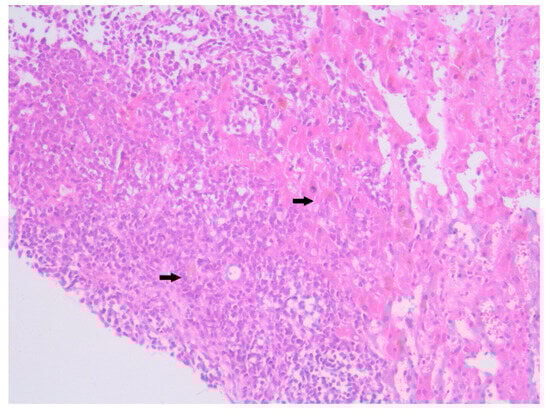

Background and Clinical Significance: Merkel cell carcinoma (MCC) is a rare, aggressive neuroendocrine cutaneous malignancy with increasing incidence among elderly, immunocompromised patients or individuals exposed to ultraviolet radiation. Case Presentation: We present the case of an 84-year-old Caucasian male with no history of [...] Read more.

Background and Clinical Significance: Merkel cell carcinoma (MCC) is a rare, aggressive neuroendocrine cutaneous malignancy with increasing incidence among elderly, immunocompromised patients or individuals exposed to ultraviolet radiation. Case Presentation: We present the case of an 84-year-old Caucasian male with no history of immunosuppression, who was admitted for asthenia, dysphagia, weight loss, and generalized weakness. Clinical and imaging investigations revealed a violaceous tumor on the right arm and disseminated metastases affecting the liver, spleen, bones and lymph nodes. A liver biopsy confirmed a small round blue cell neoplasm suggestive for MCC, although immunohistochemistry could not be performed due to the patient’s fulminant deterioration and death within 12 days of admission. Conclusions: This case is notable for its exceptionally rapid progression, particularly splenic involvement, and absence of known immunosuppressive factors. It highlights the existence of highly proliferative MCC subtypes with potential for bypassing classical metastatic pathways. Early clinical suspicion and prompt histological evaluation are essential for diagnosis, although the prognosis remains poor in advanced stages. Due to fulminant deterioration, immunohistochemistry could not be performed; therefore, the diagnosis is highly suggestive based on clinical, imaging, and morphological correlation. Full article